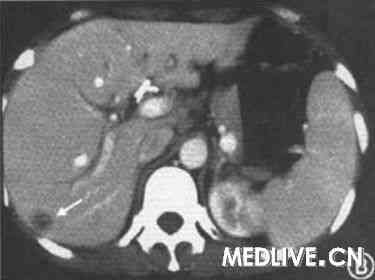

,提示肝、脾肿大。为进一步诊治收住我院消化科。![]() |

未见异常。胰腺CT:胰头体积增大,余未见胰管扩张;腹膜后淋巴结肿大并肝、脾肿大。纤维胃镜